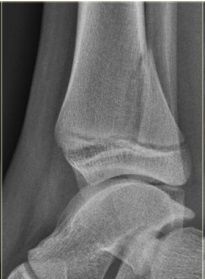

What disease is this? | Osteoarthritis |

What disease is this? | Rheumatoid arthritis |